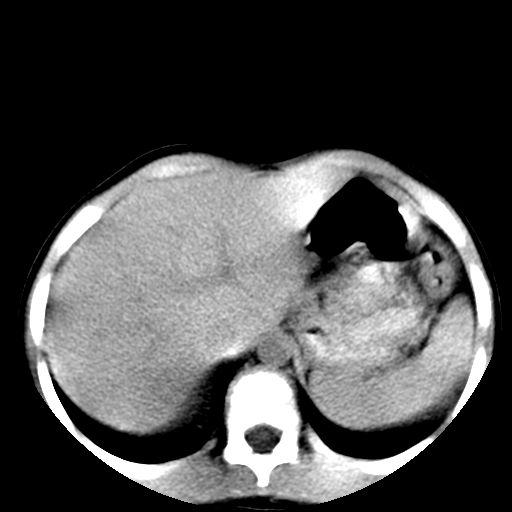

腹部好象未见异常。

腹部ct平扫未见明确异常

腹部ct平扫不能提示哪里有病变。